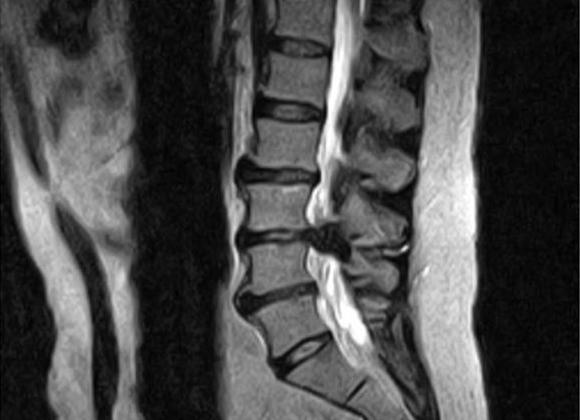

Этот диагностический метод имеет массу преимуществ, поэтому широко применяется во всех сферах медицины. Сущность МРТ заключается в воздействии магнитным полем на локтевой сустав и получении резонанса в виде радиосигналов.

МРТ локтевого сустава дает возможность получить точный результат исследования таких структур дистальной части плеча и проксимальной части предплечья: